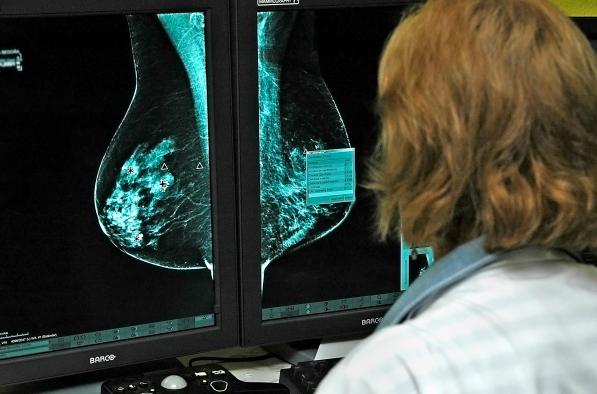

El Hospital General Universitario de Ciudad Real, dependiente del Servicio de Salud de Castilla-La Mancha, ha abierto una nueva línea de investigación relacionada con el cáncer de mama.

El objetivo es determinar si se puede minimizar la agresión de la cirugía en los dos tipos de cáncer de mama más agresivos, el triple negativo y el Erb positivo, manteniendo el máximo control de la enfermedad.

Se trata de la primera investigación sobre cáncer de mama que se realiza en la Gerencia de Atención Integrada de Ciudad Real con líneas celulares cancerosas. Tal y como ha explicado el jefe del servicio de Cirugía del hospital ciudadrealeño, Jesús Martín, lo que pretenden es “evitar hacer más cirugía en la axila de la necesaria, porque debido a la quimioterapia nos induce a error al valorar las muestras de anatomía patológica de la axila”.